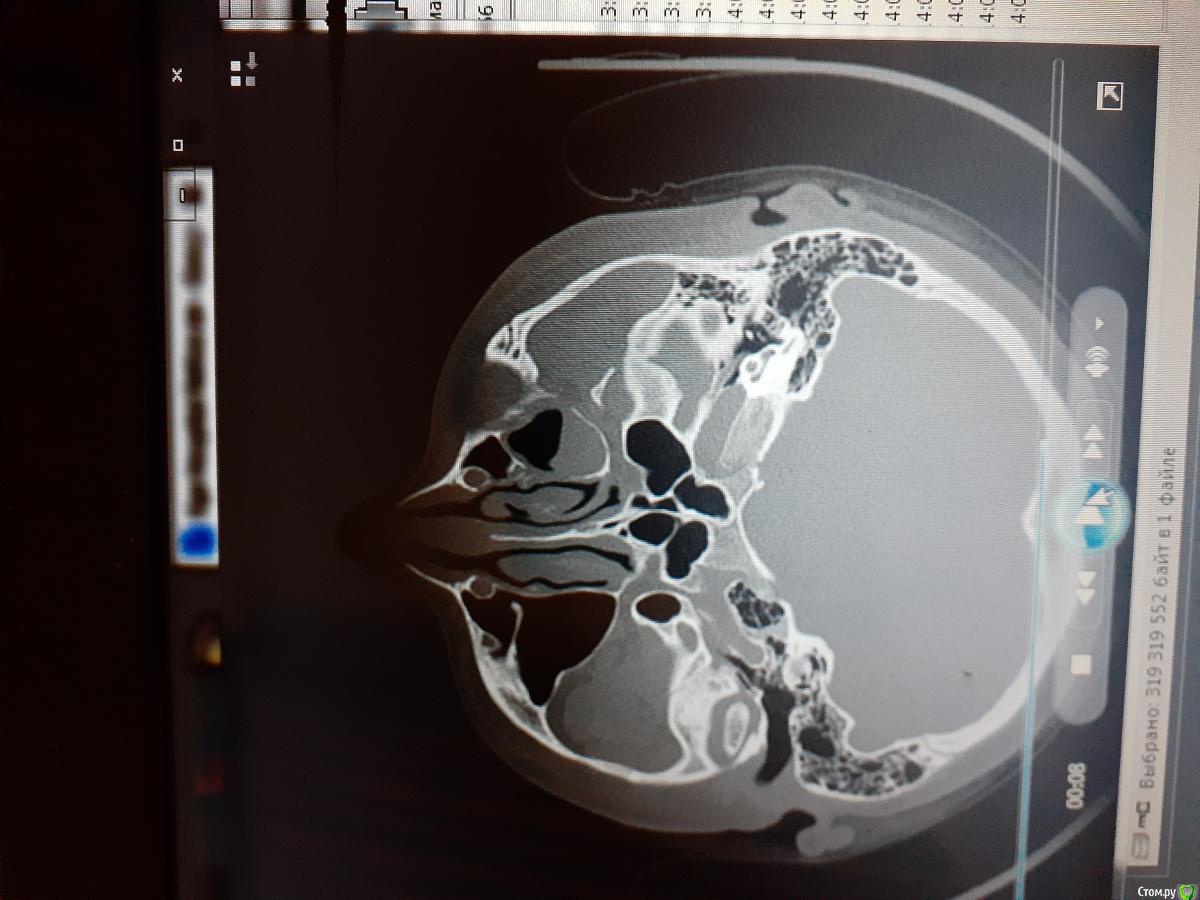

Kainat Опубликовано 22 августа, 2020 Поделиться Опубликовано 22 августа, 2020 Здравствуйте, уважаемые форумчане!У пациентки перелом скуловой кости. Жалобы на ограничение открывания рта, онемение подглазничной области. Была проведена репозиция по Лимбергу. После репозиции немножечко улучшилось открывание рта. Прошел месяц, деформации не наблюдается, однако у пациентки пока сохраняется онемение, в щечной области правда восстановилась чувствительность. Основная жалоба на ограничение открывания рта (2пальца). Может ли это быть связана с мышечной контрактурой, т.к. отек мягких тканей был очень сильным и до сих пор полностью не прошел. Данные кт прилагаются (первые три рисунка до репозиции). Благодарю заранее! Ссылка на комментарий

Irouil Опубликовано 23 августа, 2020 Поделиться Опубликовано 23 августа, 2020 Вы видите причину ограничения открывания рта? Могу выслать видео кт...Не вижу, просто без структурных причин месяц контрактуры я не встречал. Можете выложить просто на файлообменник В смысле деформации костной ткани не наблюдается, симптом ,,ступеньки" не наблюдается...Теперь ясно. По предоставленным срезам репозиция успешная. Может гематома инкапсулированная где-то, гемосинус был Ссылка на комментарий